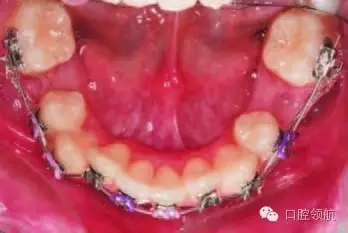

圖3.6中使用的是熱激活-鎳鈦弓絲,這種弓絲在初期排齊階段的優(yōu)勢是什么呢?

初期排齊階段使用的弓絲,應有足夠大的有效限度,較小的剛度,還需要有足夠的強度抵御咬合力。鎳鈦絲除了具備上述特點外,還有形狀記憶性、配合其良好的柔韌性,適用于嚴重錯位牙及扭轉牙的排齊。良好的彈性還使得它在任意程度的彎曲形變時都能夠持續(xù)釋放適宜大小的正畸力。